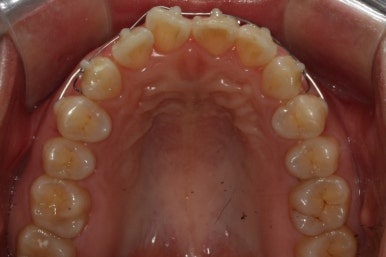

부산앞니교정 키다리아저씨치과에 처음 내원하셔쓸 당시의 입안 모습입니다.

앞니가 살짝 삐뚤어진 것을 볼 수 있고, 삐뚤어진 사이에서 약간의 틈새도 있었습니다.

예전에 치료 받으셨던 앞니 부분에 약간의 변색도 와서 미적으로 좋지 못한 상황이였습니다.